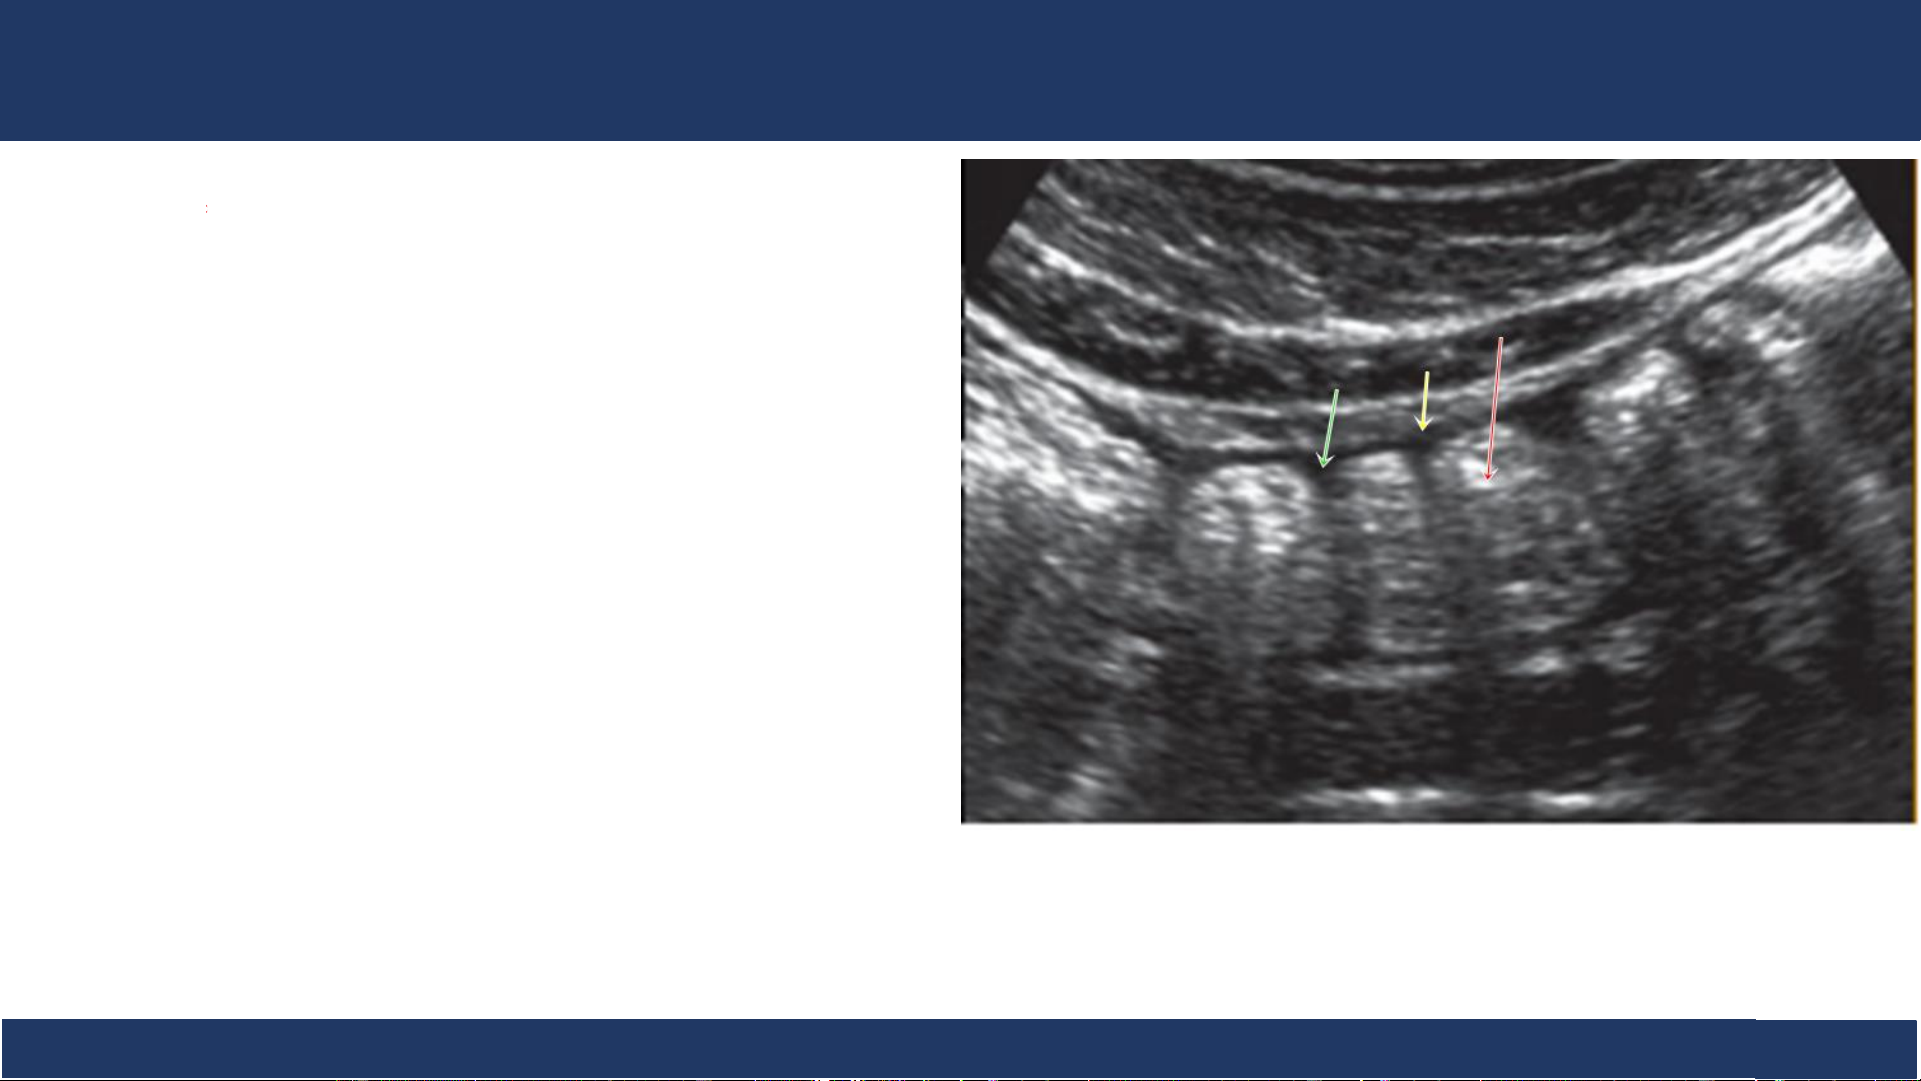

hình ảnh, ĐHYD TPHCM 17 SA: đại tràng Đại tràng . - Lòng chứa hơi (mũi tên đỏ) cho bóng lưng dơ) - Thành (mũi tên vàng) - Có nếp bán nguyệt (mũi tên xanh) Bệnh v B iệ ộ môn n Nh Chẩ i Đồng n đoán 1

hình ảnh, ĐHYD TPHCM 18 SA: đại tràng